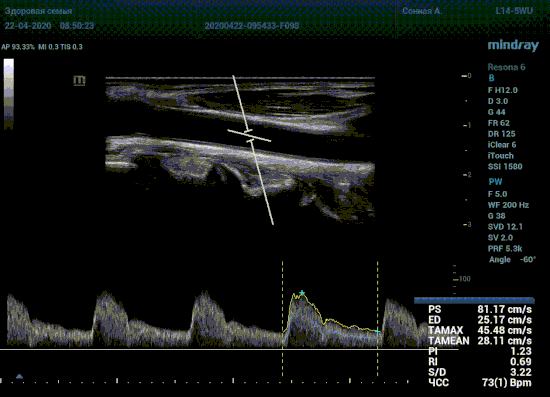

Какие показатели выдает автоматический расчет? Доктор может настроить расчет под себя, под свои собственные желания. Стандартно выставлены показатели пиковой (PS) и конечной диастолической скорости (ED), TAMAX, TAMEAN, Pi, Ri, S/D соотношение и ЧСС. Можно дополнить из списка показателей: MD, PPG, Объемный поток, DT, AT, MPG, MMPG, VTI, D/S соотношение. Прибор подстраивается под Вас, а не вы под прибор.